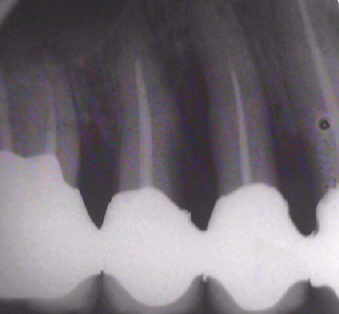

Auffällig ist, dass sich der Erfolg der Maßnahme trotz der ausgesprochen ungünstigen Voraussetzungen eher in Zentimetern als in Millimetern messen lässt, wobei die Sondierungstiefen dem Röntgenbefund entsprechen. Dies, obwohl es sich eher um eine Verzweiflungstat unsererseits gehandelt hat, keine Membran benutzt wurde, lediglich Cerasorb ohne zusätzlichen Eigenknochen eingebracht wurde, es zur zweimaligen Nahtdehiszenz mit anschließender sekundärer Wundheilung kam, man die Caerasorb-Kügelchen längere Zeit klinisch freiliegend beobachten konnte.

Unstrittig ist, dass absolute Entzündungsfreiheit eine entscheidende Rolle spielt. Wir glauben, dass der zweite wesentliche Erfolgsfaktor die Abwesenheit von Beweglichkeit des Zahnes ist und erklären diesen Erfolg in diesem Sinne durch:

a) die Abwesenheit von Entzündung aufgrund der Wurzelfüllung nach sorgfältiger Desinfektion, also der Vermeidung einer möglichen Reinfektion aus der Pulpa und den Tubuli heraus

b) die absolute Ruhigstellung durch die primäre Verblockung

c) natürlich durch den konsequenten Gebrauch von Interdentalbürstchen zur Vermeidung einer Reinfektion von oben